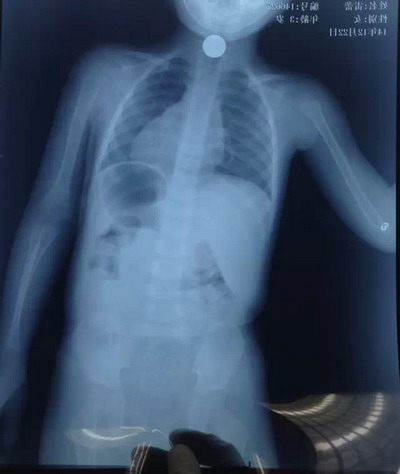

2014年12月22日下午一名2岁的幼儿不小心误吞咽了一枚1角硬币,情况非常紧急,幼儿随时有生命危险,硬币刚好卡在食管上段近声门处,由于幼儿食管腔狭小、管壁薄、黏膜已损伤,硬币较大不能移动,加上患儿哭闹不能配合操作,内镜操作的难度是非常大的。但消化内科唐少波主任在麻醉医师、内镜护士的密切配合下,凭借精湛而娴熟的技术,仅用了数分钟就顺利取出了危胁患儿生命的食管异物,患儿的家长感激不尽。